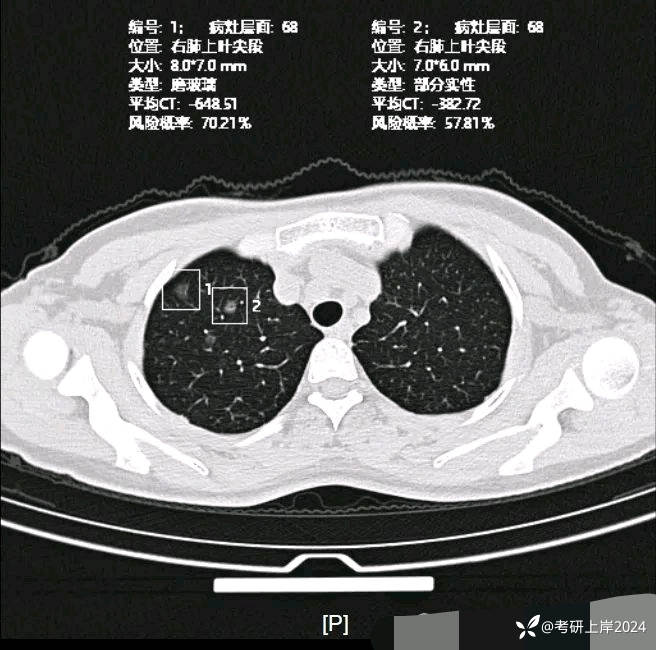

患者最近的检查有AI辅助诊断意见,找出的病灶分别如下:

病灶1:右上叶长径8毫米纯磨玻璃结节,边上有微小血管贴着,整体轮廓较清,怕哪样欠均匀。考虑不典型增生或原位癌可能性大;

病灶2:右上叶长径7毫米磨玻璃结节,密度稍高,但仍未达纵隔窗可见的实性密度,中间有小空泡征,轮廓与边界清,考虑原位癌或微浸润性腺癌可能性较大;